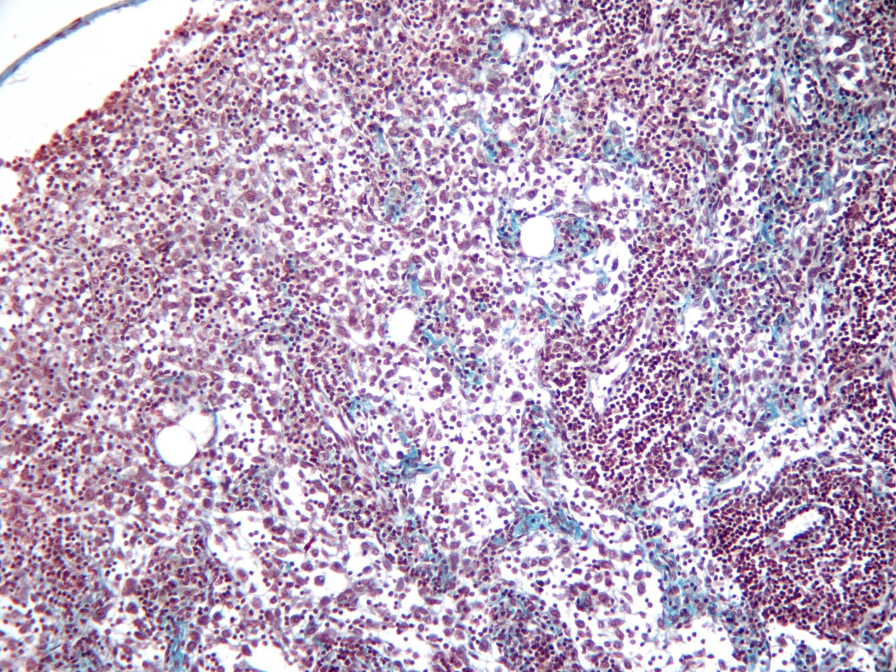

Estructura ganglio linfático

Ganglio linfático

Corteza:

externa - folículos linfáticos

interna - tej linfoide difuso + vénulas del endotelio alto

fibras reticulares del estroma - verde

en verde - folículo linfático secundario con su centro germinativo

Vénulas del endotelio alto - corteza interna